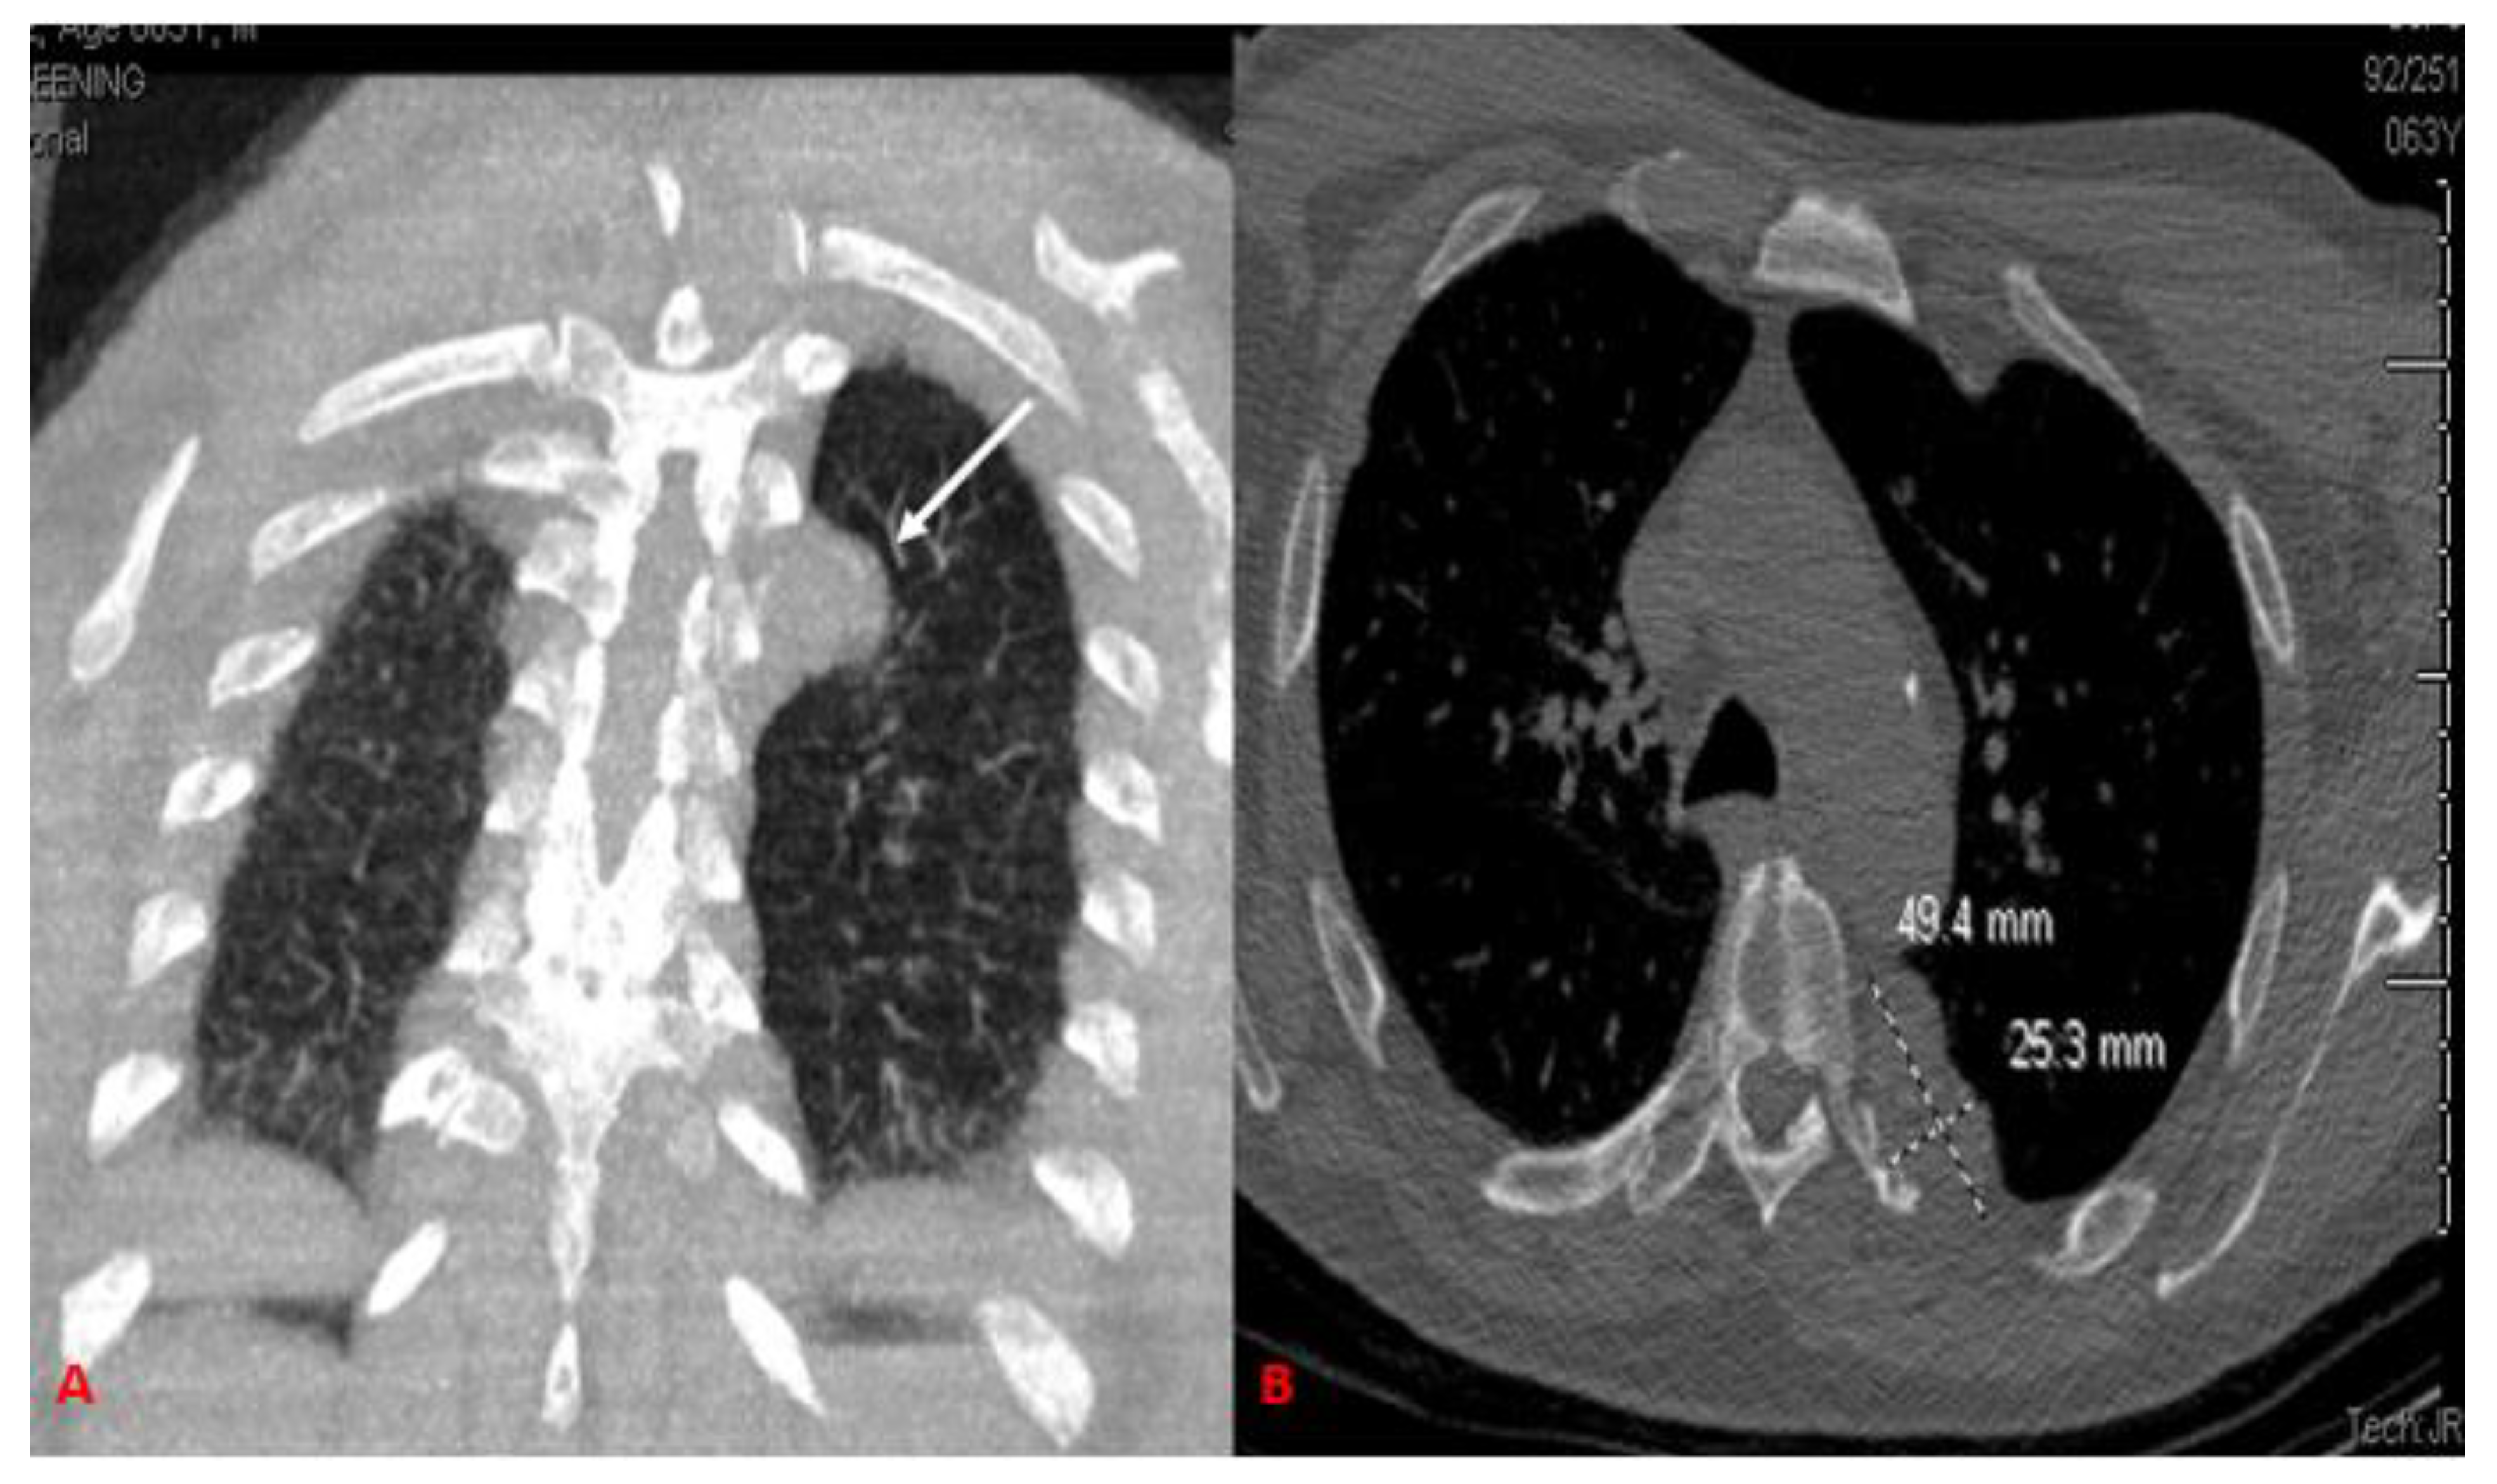

2. Case Report

| Present case (2022) | 52/M | Dyspnea on exertion | 4.9 × 3.9 × 2.5 | Complete surgical resection | 6-month follow up, symptom-free with no recurrences |